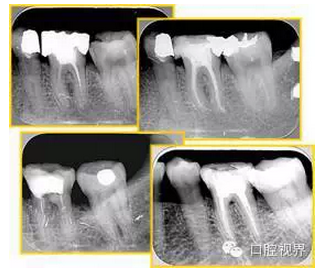

左圖和上圖為干髓治療后牙齒,齲齒疏通后進(jìn)行根管充填。

如圖為塑化加根充處理后牙齒 X 線片。

6. 鈣化

常見有修復(fù)性鈣化和增齡性鈣化。下面為根管鈣化 X 線片。

右圖及下圖為器械折斷的 X 線片。箭頭處示折斷器械。